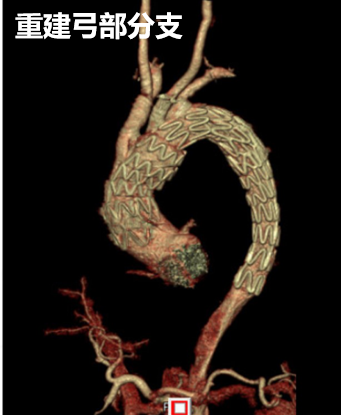

重建弓部分支,消除病变

弓上分支重建+

近端延伸支架

再干预方案:分支支架置入无名动脉,LCCA,LSA针刺原位开窗(方法:向近端延展)。

术前

术中

术后一周

术后4个月